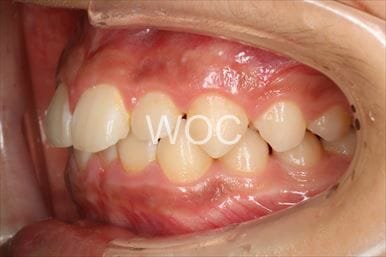

過蓋咬合

治療前1

治療前2

治療前3

治療前4

治療前5

- 年齢:10歳8ヶ月

- 主訴:出っ歯、ガタガタ

- 診断名:過蓋咬合、叢生、上顎前突

- 装置:可撤式拡大装置、機能的矯正装置

- 期間:2年7ヶ月 ※

- 費用:基本矯正料金:390,000円